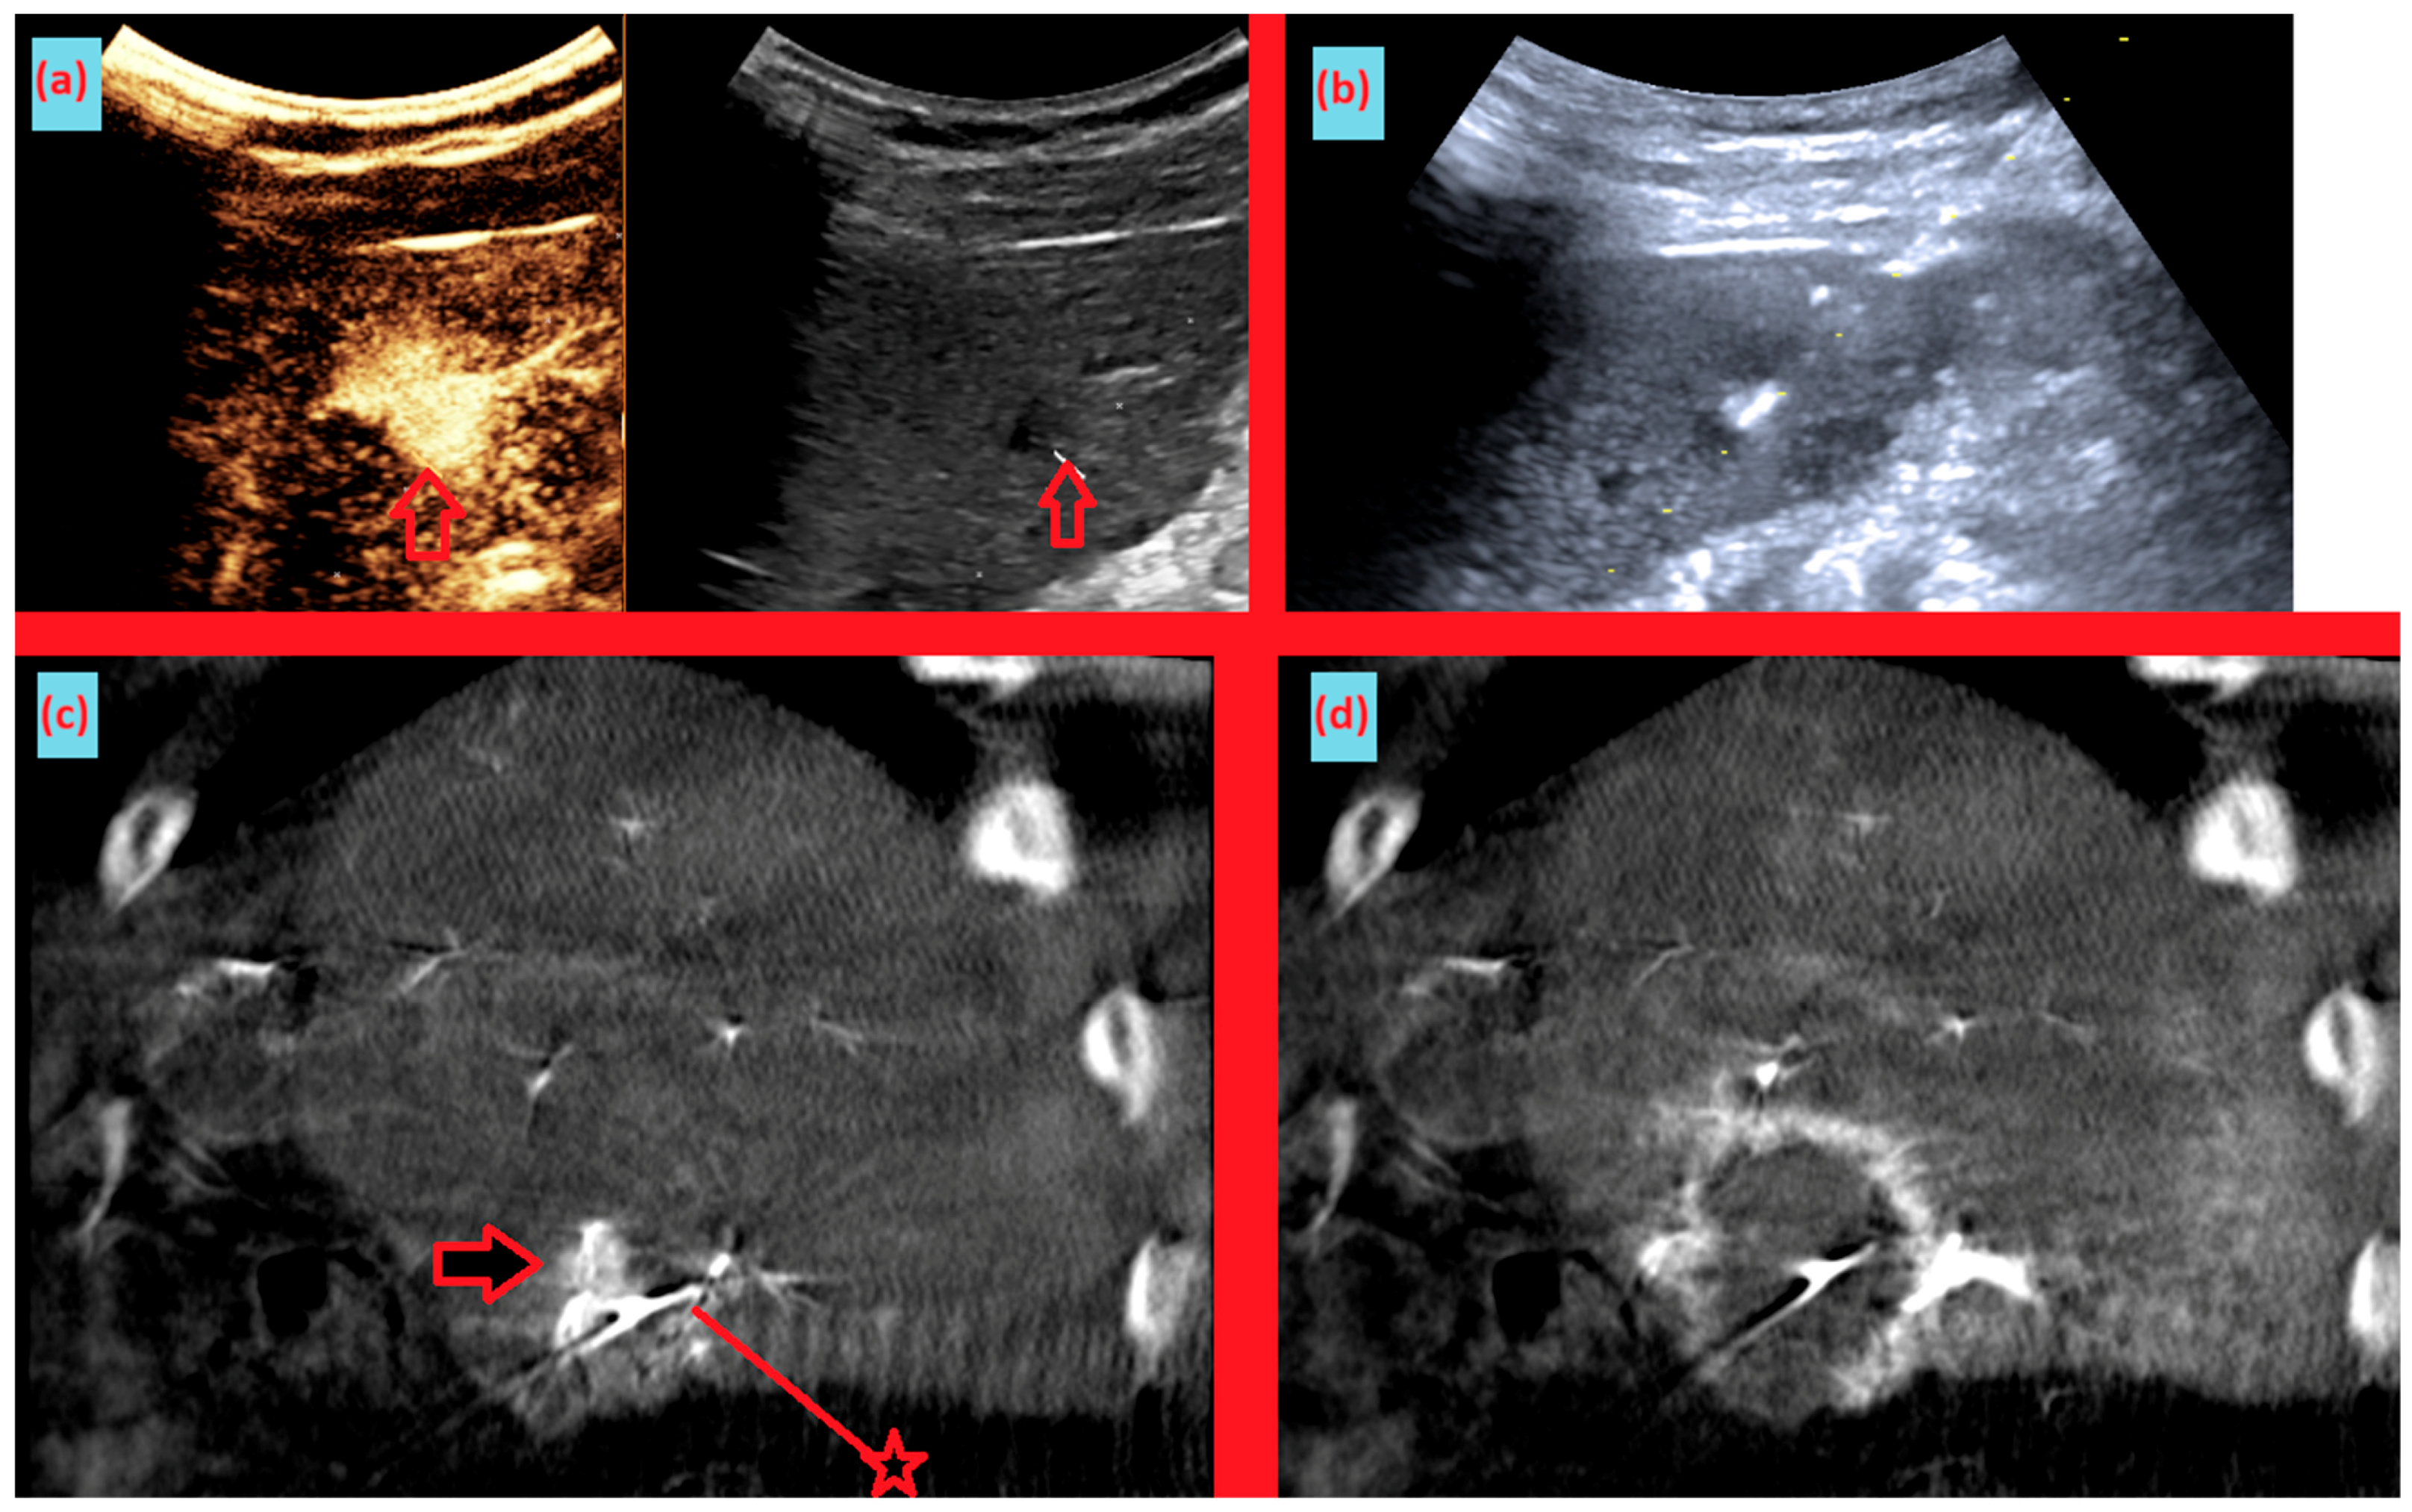

As shown in Figure 1, angio-CBCT allows for higher visibility of the target mass, as reflected in the ΔHU values. This can be visually confirmed in several cases. Representative cases in Figure 2 and Figure 3 demonstrate how the target mass is much more conspicuous to the operator on angio-CBCT compared to pre-procedural CT. In Figure 4, a mass, which was nearly invisible on pre-procedural CT, was identified through angio-CBCT, aiding the targeting process. Figure 5 shows a case where a mass with discordance between USG and CEUS was confirmed using angio-CBCT, leading to needle repositioning and achieving complete ablation. Finally, Figure 6 illustrates a case where a residual tumor was identified on angio-CBCT and re-ablation resulted in complete ablation.

Figure 5. Images from another patient with hepatocellular carcinoma undergoing angio CBCT-guided RFA. (a) Pre-ablation CEUS and B-mode ultrasound demonstrating discordance between the CEUS-enhancing area and the hypoechoic lesion on B-mode. (arrow = mass) (b) During RFA, ultrasound-guided needle insertion was performed, targeting the hypoechoic lesion on B-mode. (c) Sagittal reformatted angio CBCT obtained after the initial needle placement shows the needle positioned inferior to the enhancing tumor. After review, the needle was repositioned slightly superiorly. (arrow = mass, line with star = RFA needle) (d) Sagittal reformatted angio CBCT after ablation demonstrates an adequate ablation zone with complete loss of lesion enhancement, consistent with complete ablation.